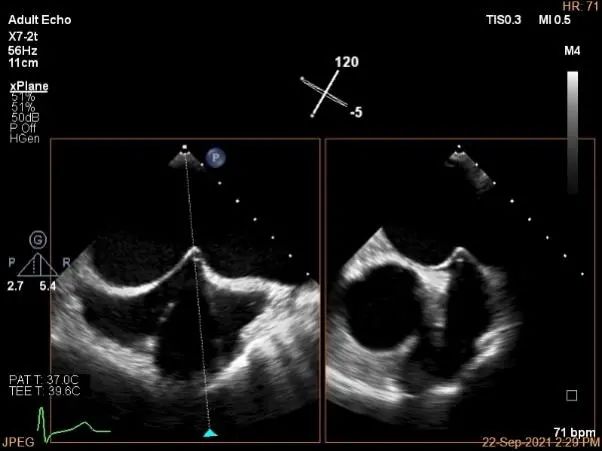

术中超声

P2区脱垂,宽14.8mm,Gap:3.3mm

3D-color,返流重度,3+级

房间隔穿刺点选择

穿刺高度:4.3cm